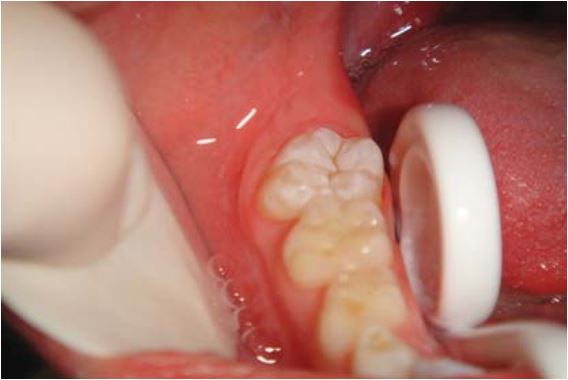

Sealant giúp ngăn ngừa sâu hố rãnh ở răng cối vĩnh viễn ở trẻ. Răng cối vĩnh viễn mới mọc thường xốp và dễ bị sâu. Men răng trưởng thành sau 62 tháng kể từ khi mọc. Trám sealant càng sớm càng giúp giảm tỉ lệ sâu hố rãnh. Nguy cơ sâu răng cao nhất là trong năm đầu tiên kể từ khi mọc răng.

Răng mọc lên chưa hoàn toàn

Trám sealant cho những răng này thường khó vì khó cách li, do đó khuyến cáo trám bằng các vật liệu ưa nước như GIC hoặc sealant GIC (Vitrebond). Răng được theo dõi liên tục cho đến khi mọc lên hoàn toàn, lúc đó sẽ thay lớp GIC bằng sealant.